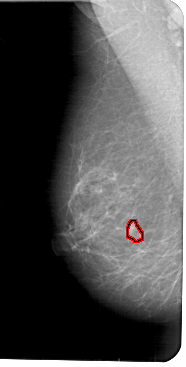

A_1776_1.RIGHT_CC

RIGHT_CC LINES 5236 PIXELS_PER_LINE 2446 BITS_PER_PIXEL 12 RESOLUTION 43.5 NON_OVERLAY

FILE: A_1776_1.LEFT_CC.OVERLAY

TOTAL_ABNORMALITIES 1

ABNORMALITY 1

LESION_TYPE MASS SHAPE IRREGULAR MARGINS ILL_DEFINED

ASSESSMENT 4

SUBTLETY 3

PATHOLOGY BENIGN

TOTAL_OUTLINES 1

BOUNDARY